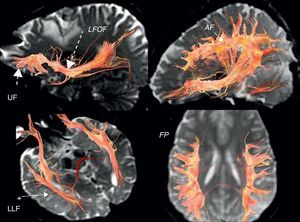

In the case of subcortical “functional” fasciculi, there was 100% concordance. The correlated bundles were (Table 3) (Fig. 2):

Arcuate fasciculus: medial part of the superior longitudinal fasciculus, connecting the frontal lateral and parietotemporal.

Frontoparietal fasciculus or bundle: lateral part of the superior longitudinal fasciculus, connecting Broca's area with the lower parietal lobe.

Lower frontooccipital fasciculus: it connects medial occipito-temporoparietal and prefrontal areas. In its anterior third it is located cranially to the ceiling of the temporal horn and the optic radiations. In its posterior temporooccipital segment it is lateral in relation to the ventricular occipital horn, becoming part of the sagittal stratum. It ends in the medial temporoccipital cortex.

Lower longitudinal fasciculus: in its left temporooccipital tract it is involved in identifying the form of objects or “visual object-form area”.

Subcallous fasciculus: it surrounds the ventricular frontal horn and connects the supplementary motor area with the cingulum and the caudate nucleus.

3D tractography. Functional subcortical fasciculi implicated in language. AF: arcuate fasciculus (short continuous arrow); LFOF: lower frontooccipital fasciculus (long discontinuous arrow); LLF: lower longitudinal fasciculus (long continuous arrow); FP: frontoparietal bundle; UF: uncinate fasciculus (short discontinuous arrow).

Another bundle identified was the uncinate fasciculus (Fig. 2) which connects the anterior frontotemporal cortex, which apparently is not involved in language. It serves as point of reference in locating the lower frontooccipital fasciculus and it is the point of departure for Meyer's ansa and the optic radiations (Fig. 3) (posterior temporooccipital tract forming part of the sagittal stratum, it lies laterally to the occipital horn, with a medial curvature toward the calcarine fissure).